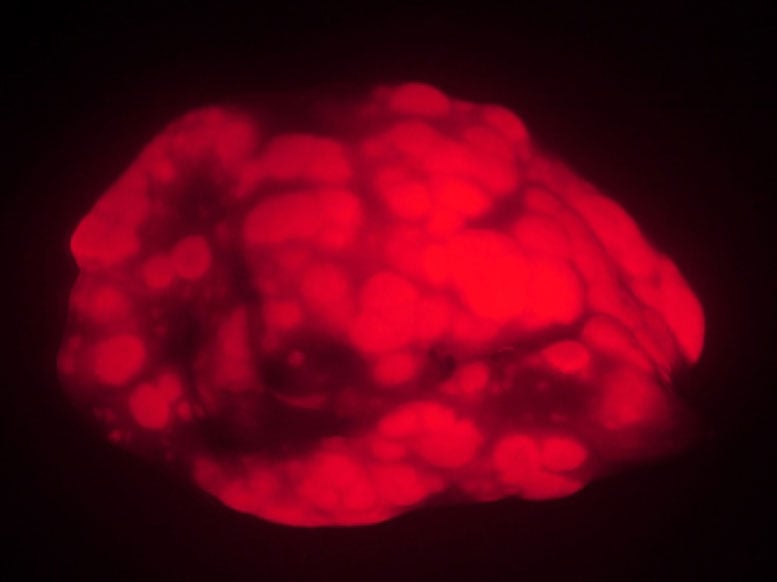

Die fünfzehn Wochen nach der Krebsinduktion durchgeführten Messungen zeigten dramatische Unterschiede. Die Lungen junger Mäuse wiesen etwa dreimal mehr Krebsgewebe auf als die der alten Tiere. Die Tumore bei den jungen Mäusen waren nicht nur zahlreicher, sondern auch signifikant größer. Diese Beobachtungen legen nahe, dass der Alterungsprozess selbst eine schützende Wirkung gegen die Krebsentwicklung ausüben könnte, ein Konzept, das neue potenzielle therapeutische Perspektiven eröffnet.

Alte Mäuse entwickeln weniger Lungentumore (rot) und kleinere Tumore als junge Tiere in einem Krebsmodell.

Bildnachweis: Emily Shuldiner